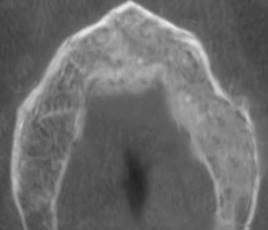

Given the patient’s systemic and local history, conservative management was performed after the patient signed an informed consent. Twice-a-day rinsing with 0.12% chlorhexidine was prescribed for 14 days, as well as pentoxifylline 400 mg tablets every 12 hours and tocopherol 1000 IU, 1 tablet every 24 hours. Antibiotic treatment with amoxicillin/clavulanic acid (875/125 mg) was also indicated for 14 days to treat the co-occurring infection. The patient was monitored after 14 days. We observed a decrease in purulent content and inflammation, with persisting communication with bone tissue. Antibiotic treatment was discontinued after one month. The rest of the treatment remained unchanged (PENTO protocol + topical antiseptics). The patient would be monitored every two weeks. The clinical behavior of the lesion was evaluated every two weeks. The lesion was cleaned and irrigated with topical antiseptic 0.12% chlorhexidine. The patient reported improved symptoms after six months. He reported decreased pain and bleeding in the affected area. There was evidence of healing of the affected mucosa, continuity disruption, absence of bleeding, and no inflammation of the surrounding tissue (Fig. 6). A control CBCT was ordered, which showed bone neoformation, no radiolucent areas, and bone tissue without alterations (Fig. 7). The patient continued to be monitored for two months, with no clinical or radiographic signs of MRONJ recurrence.

Bone neoformation and recovery of bone trabeculation with regression of radiolucent areas.